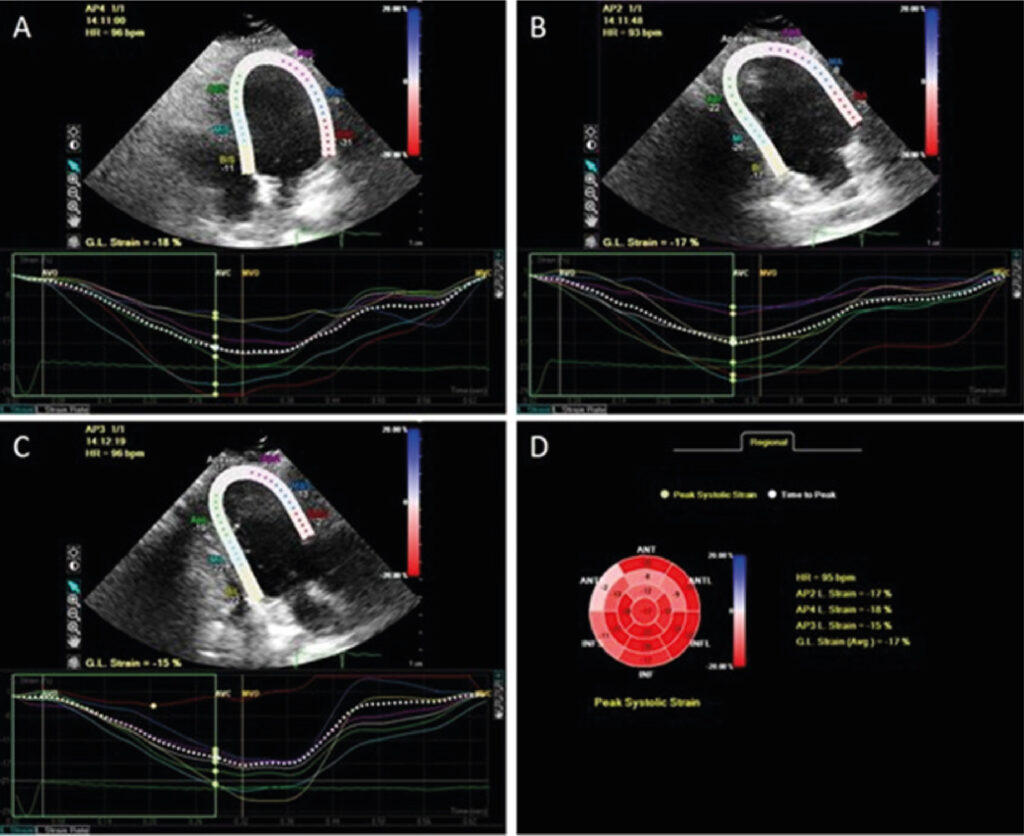

Como Eu Faço Diagnóstico e Seguimento Ecocardiográfico nas Distrofias Musculares

Neste trabalho, revisamos os aspectos mais importantes do seguimento clínico-ecocardiográfico das DM mais frequentemente associadas à cardiomiopatia, dentre elas as distrofinopatias, as DM de cintura (DMC), as distrofias miotônicas e a DM de Emery-Dreifuss (EDMD).